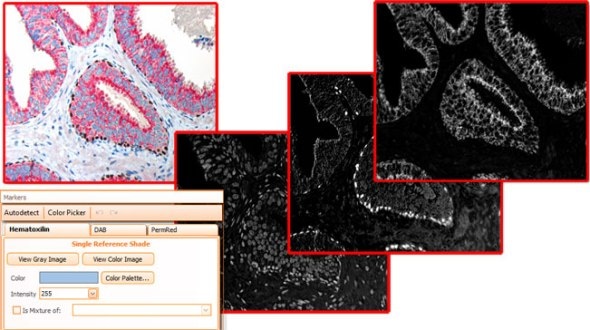

As brightfield images need to separated into images according to their colour components, HistoQuest provides two algorithms for color separation.

The first one automatically detects and separates two colors and can have a third one added (see below).

The second color separation algorithm is semi-manual (using a color picker) and separates an unlimited amount of colors with great control and precision (see image with muscle, collagen and elastin detection below).